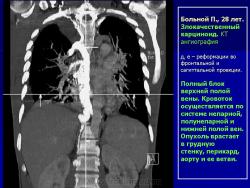

Средостение.  "Опухолевый рост".